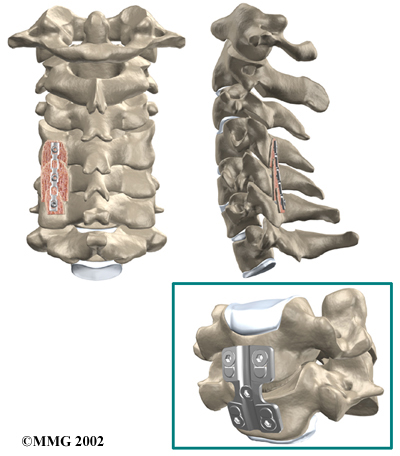

Cervical Fusion

A fusion surgery joins two or more bones into one solid bone. The purpose for doing spinal fusion is to increase the space between the vertebrae and to keep the sore joint from moving. This is usually done by placing a small block of bone graft in the space where a disc was removed. Opening up more space enlarges the neural foramen, takes pressure off the nerve roots, and eases tension on the facet joints. Cervical fusion is used to treat neck problems such as cervical radiculopathy, disc herniations, fractures, and spinal instability. There are two main types of fusion for neck problems.

- Anterior Discectomy and Fusion: Anterior discectomy and fusion is done through the front of the neck. After taking out the disc (discectomy), the disc space is filled with a small graft of bone. The bone is allowed to heal, fusing the two vertebrae into one solid bone.

Small Graft of Bone

-

The bone graft needs time to heal in order for the fusion to succeed. This requires the neck to be held still. After cervical fusion surgery, patients usually have to wear a special neck brace for several months. These neck braces are often bulky and restrictive. Recently, surgeons have begun using metal plates and screws (often referred to as instrumentation) to lock the bones in place. The instrumentation is fastened to the vertebrae, where it holds the bones still while the graft heals.

Locking the Bones in Place